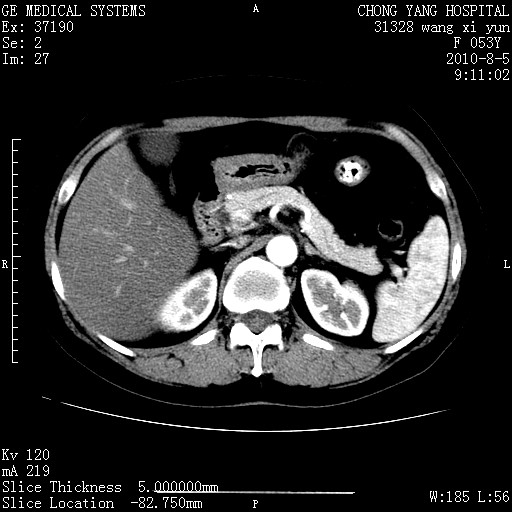

标题: CT28214:F41Y 血尿二十天,建议盆腔平扫加增强。

胆管细胞ca?

1)考虑肝左叶胆管细胞癌。2)脂肪肝。

支持胆管细胞ca。